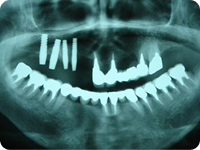

施術例②

治療前

前歯が歯周病のためグラグラで今にも抜けてしまいそうな状態です。

治療後

抜歯と同時にインプラントを植立し、3ヵ月後にセラミックの冠を装着しました。

治療前と治療8ヵ月後のレントゲン写真です。

手術時に足した人工骨も安定しています。